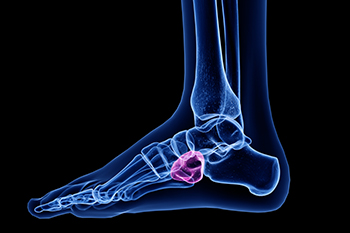

The ankle is composed of a number of muscles, bones, tendons, and ligaments. There are many conditions which may cause ankle pain.

Cuboid syndrome occurs when the cuboid bone, one of the seven tarsal bones in the foot, becomes partially dislocated or misaligned. This condition can cause pain along the outer side of the foot, swelling, and difficulty bearing weight or pushing off during walking. It often results from overuse, ankle sprains, or repetitive strain injuries from activities such as running or jumping. A chiropodist can diagnose cuboid syndrome through a physical examination and imaging, then provide treatment such as manipulation, taping, orthotics, or targeted exercises to restore alignment and relieve pain. If you have pain in this part of your foot, it is suggested that you consult a chiropodist who can accurately diagnose and treat cuboid syndrome.

The cuboid bone is one of the seven tarsal bones located in the foot. Cuboid syndrome develops when the cuboid bone moves down and out of alignment with the other bone (calcaneus bone) in the joint of the foot. Cuboid syndrome can be the result of a sudden injury like an ankle sprain, or it may develop slowly over time from repetitive tension through the bone and surrounding structures.